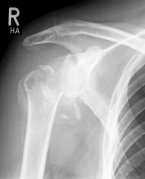

left: X-ray image of an omarthrosis

right: X-ray of a healthy shoulder joint